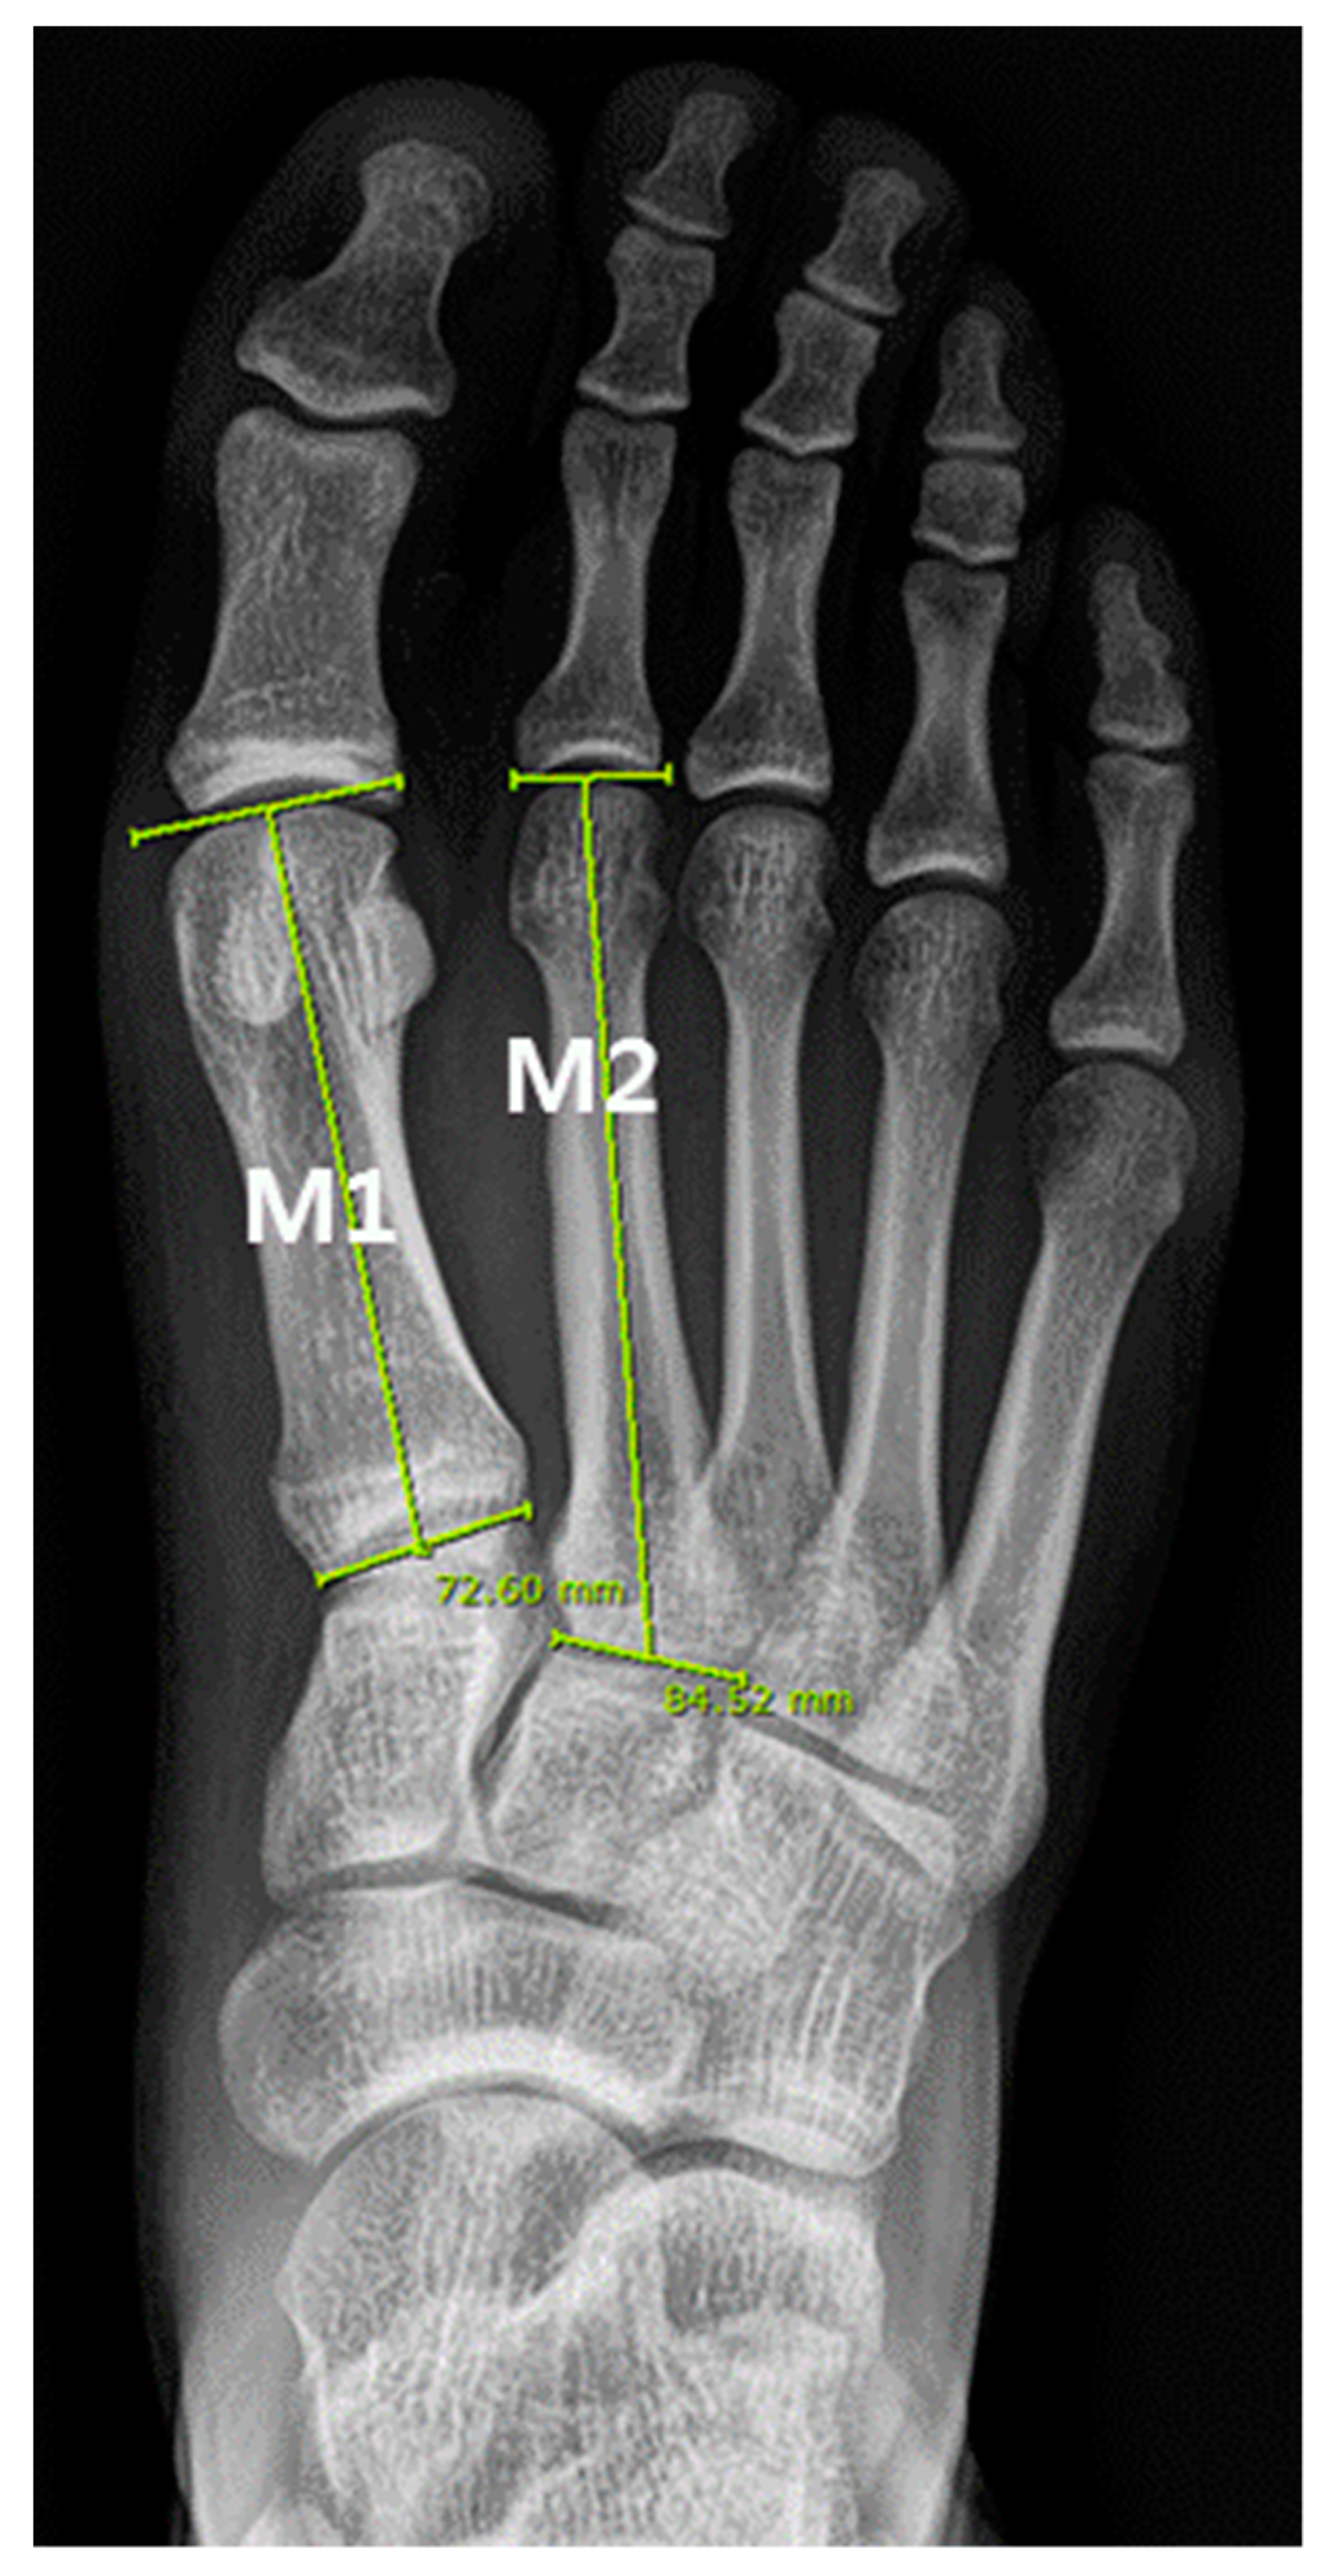

2.3. Measurement of Metatarsal Bone

| M1 (mm) | 67.27 ± 7.21 | 68.59 (62.89, 71.99) | 52.34 to 84.16 | 70.04 ± 8.57 | 72.57 (61.57, 75.95) | 52.48 to 87.99 |

| M2 (mm) | 77.66 ± 8.93 | 77.62 ( 72.41, 84.4) | 53.77 to 95.98 | 81.09 ± 9.61 | 82.71 (71.43, 88.93) | 62.23 to 101.72 |